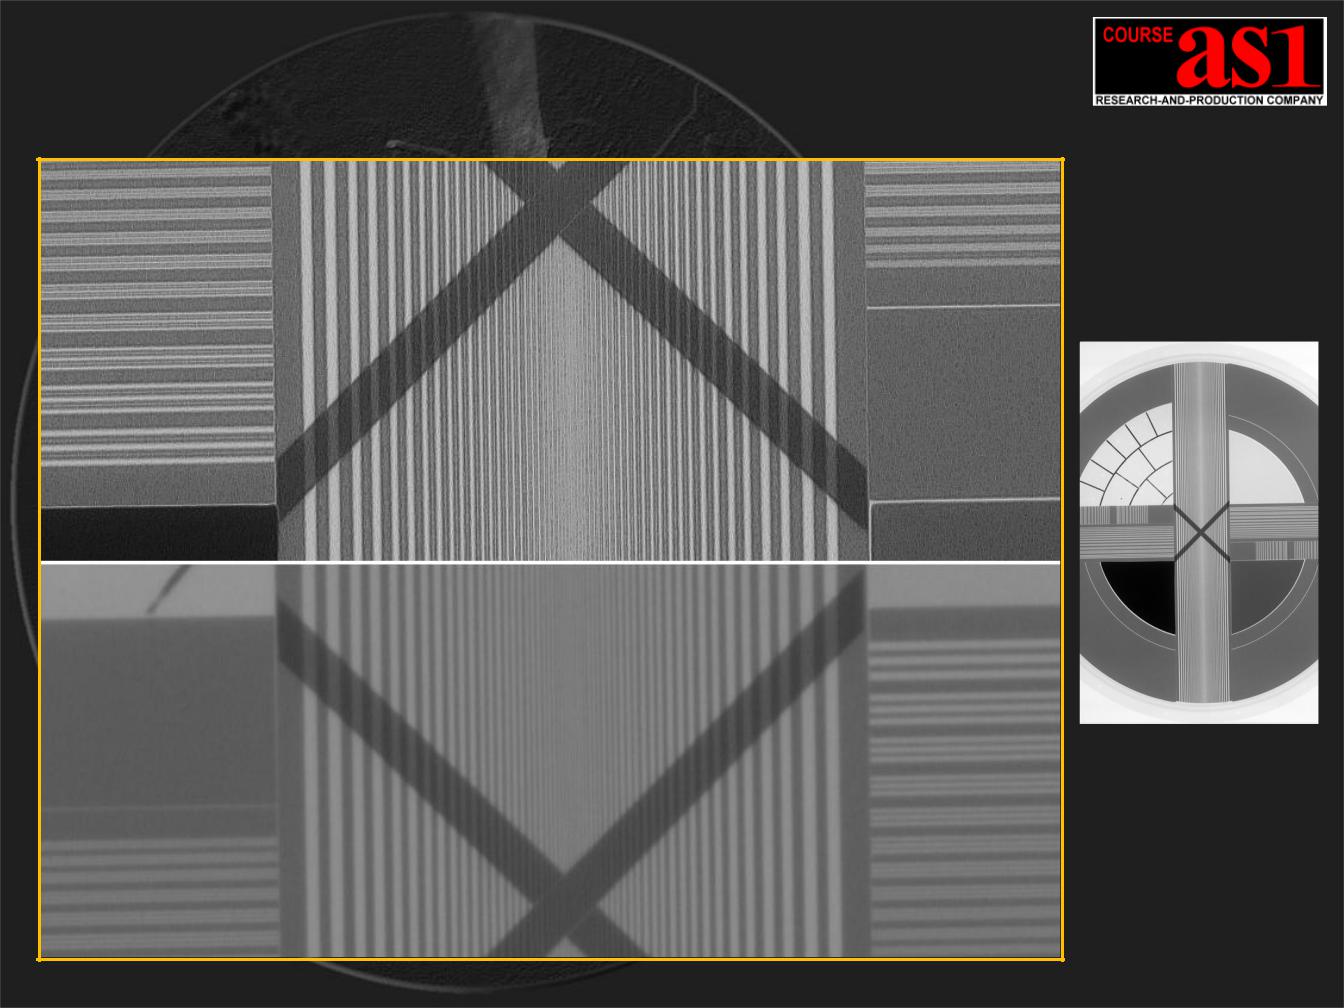

Результаты обработки X-Ray теста Siemens d=270mm 16 битного Гибкого Адаптивного Конвейера

Внизу - фрагмент исходного изображения рентгеновского теста, соответствующего средней плотности легких пациента.

Вверху - фрагмент изображения после прохождения конвейера 2D Обработки и Визуализации.

Размер рентгеновского фокусного пятна съемки:

0.6 x 0.6 мм

Режим съемки теста:

U = 60kV, I = 200mA, t = 0.1sec, ( 20 mAs )

Размер фрагмента кадра:

H x V = 85 x 42 мм

Обработка X-Ray теста Siemens (пиксельный М 1:1)

Выделен элемент теста H x V = 73 x 29 mm ( 857 x 333 pix. )

Размер пикселя = 85 микрон